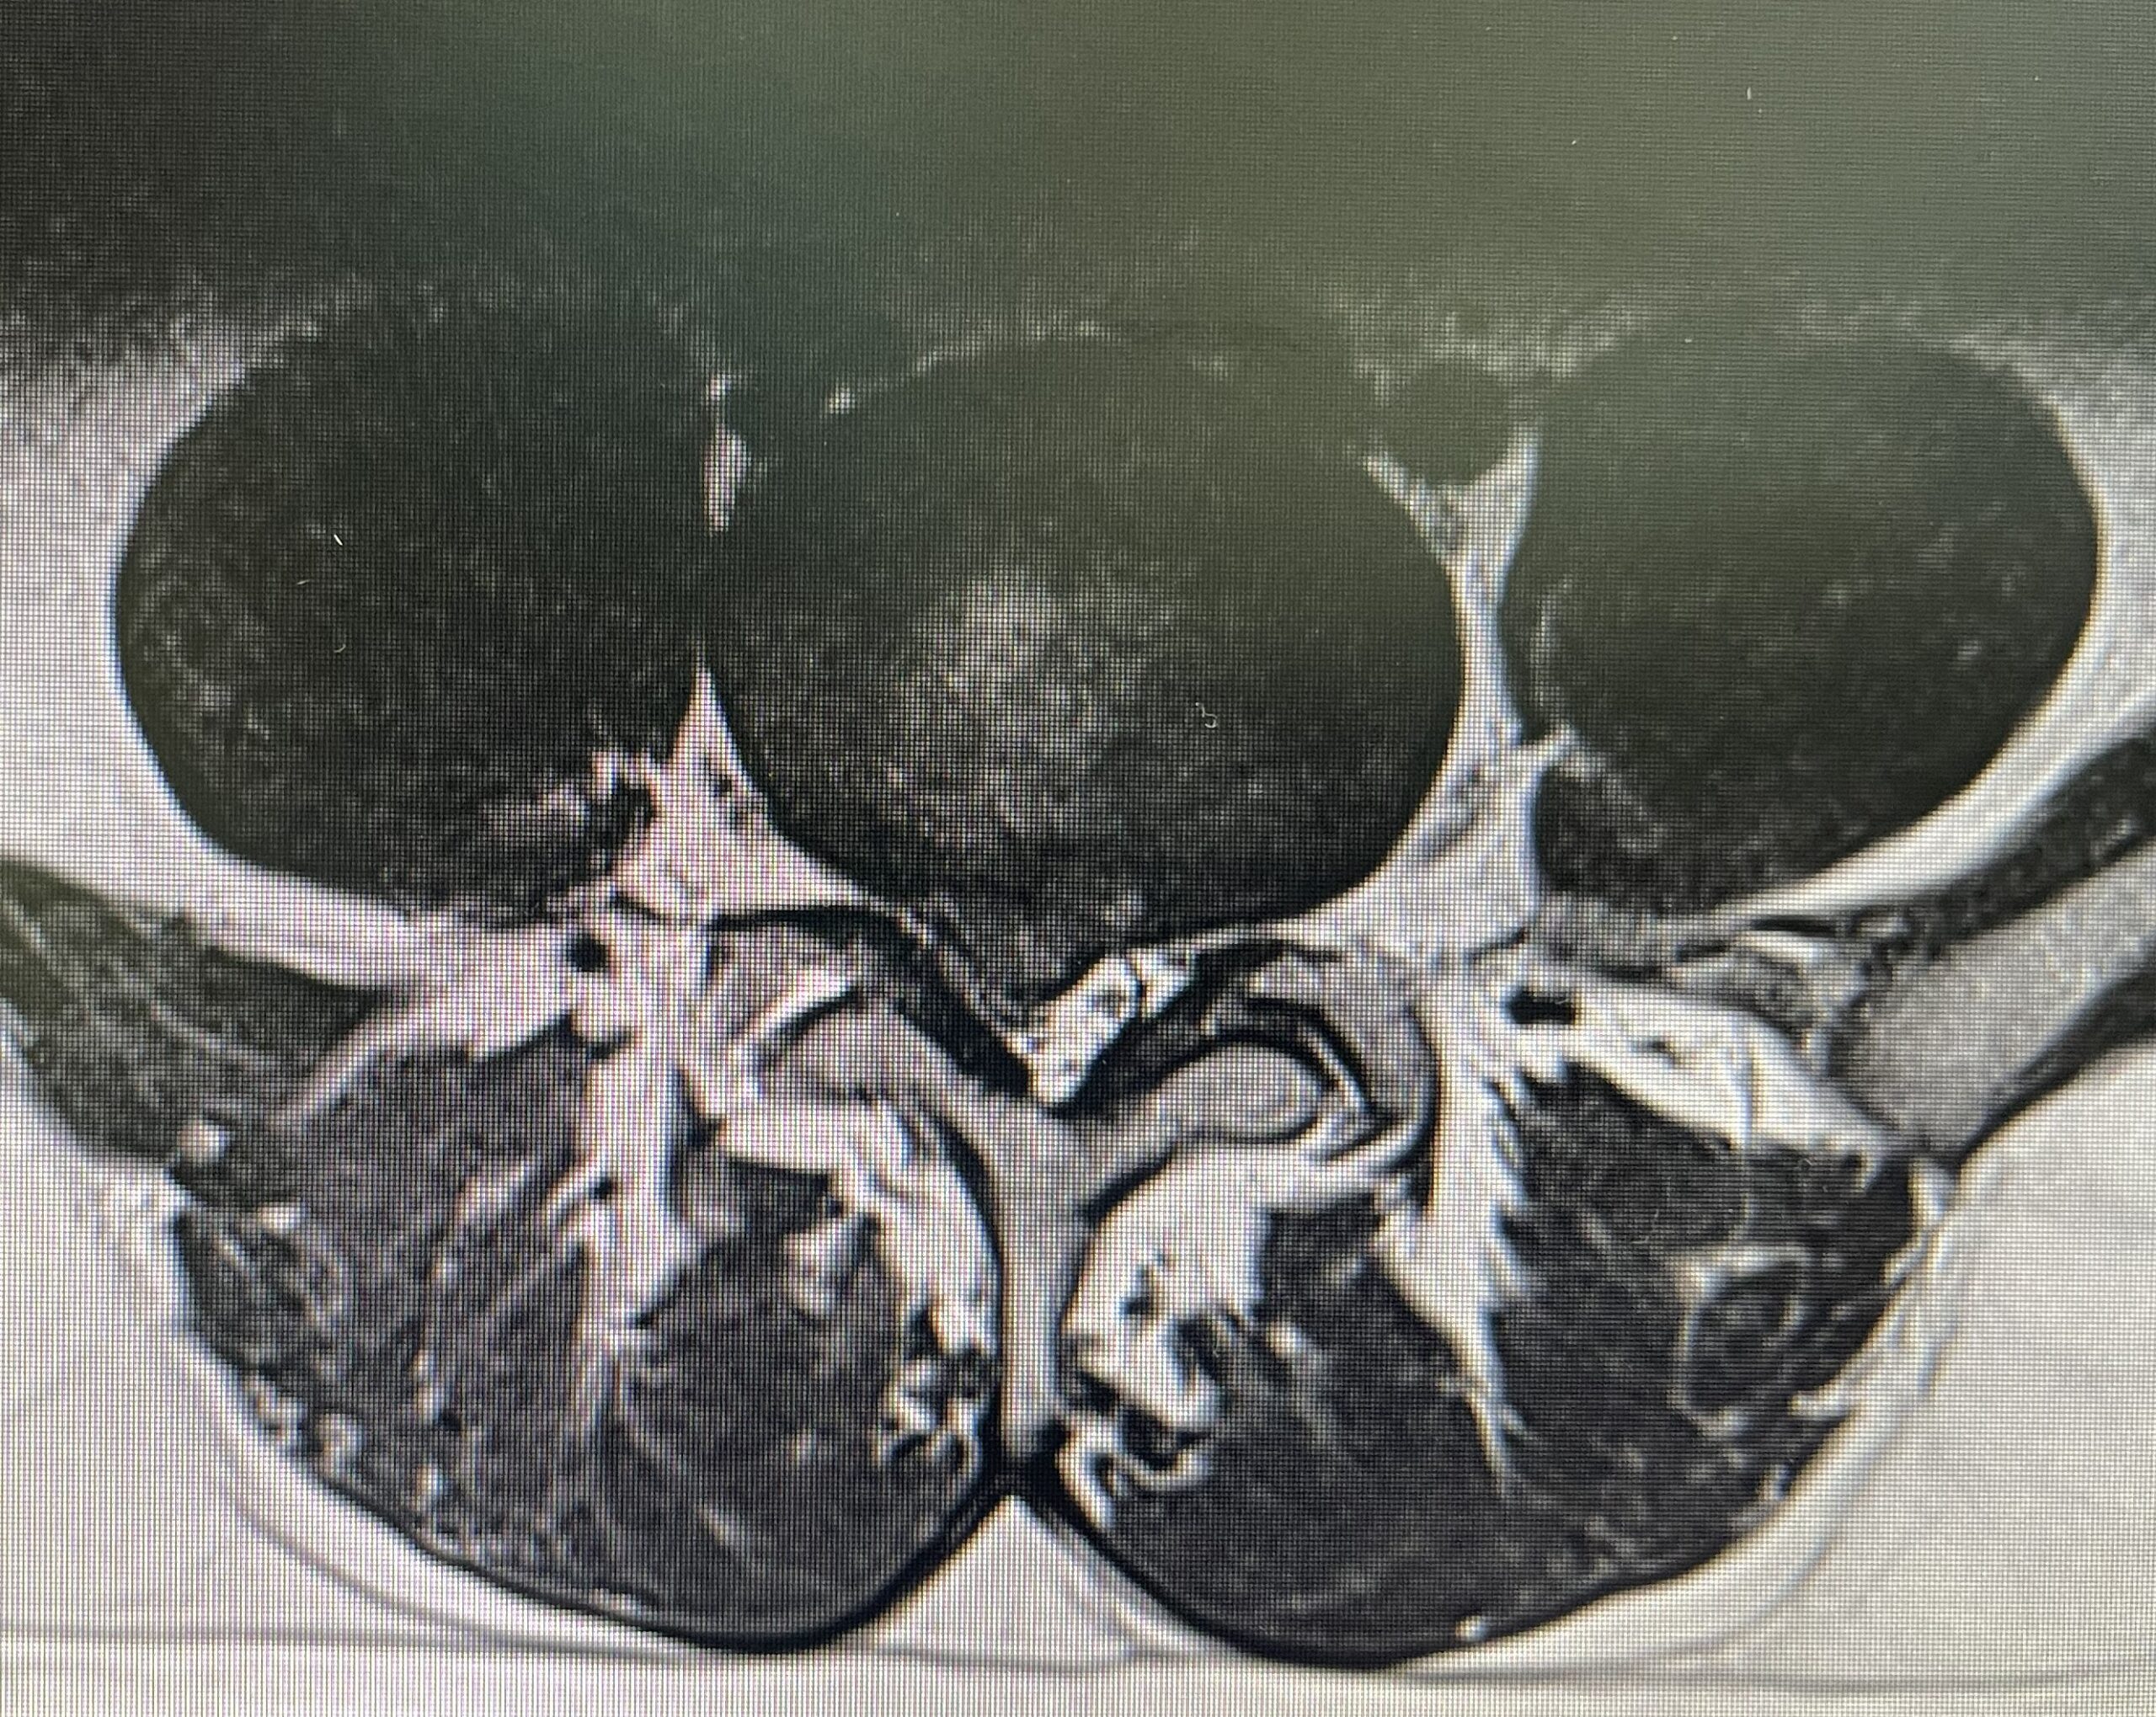

Microscopic discectomy is a minimally invasive surgical technique used to remove herniated disc material that is pressing on the spinal nerves. Unlike traditional open surgery, which involves large incisions and extensive muscle dissection, microscopic discectomy uses specialized microscopes and instruments to access the spine through small incisions. By removing the herniated disc material, microscopic discectomy aims to relieve pain, improve mobility, and promote healing of the affected area.

4. Disc Removal: Using specialized instruments, the surgeon carefully removes the herniated disc material that is pressing on the spinal nerves.

5. Nerve Decompression: Any bone spurs or thickened ligaments compressing the nerves are also removed to relieve pressure.